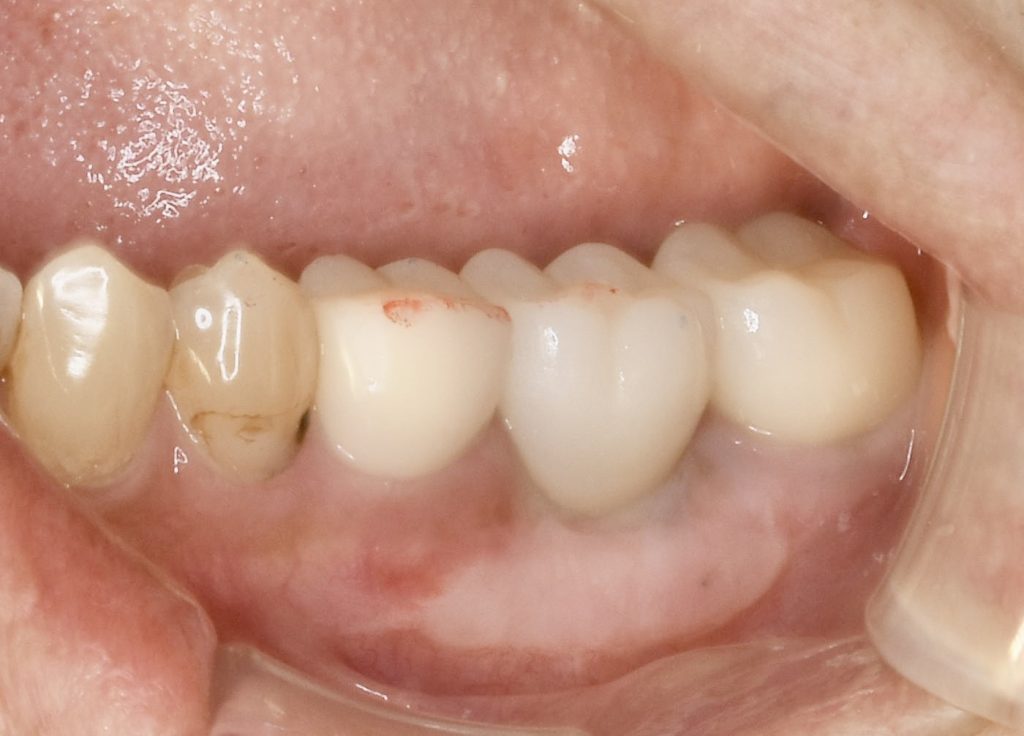

骨の再生のみならず、歯肉も不足していた為、歯肉移植を行いメンテナンスしやすい環境を整えました。

これにより長く機能させる事が可能となったと思います。

下記の症例にかかる費用    約72万円(税抜)